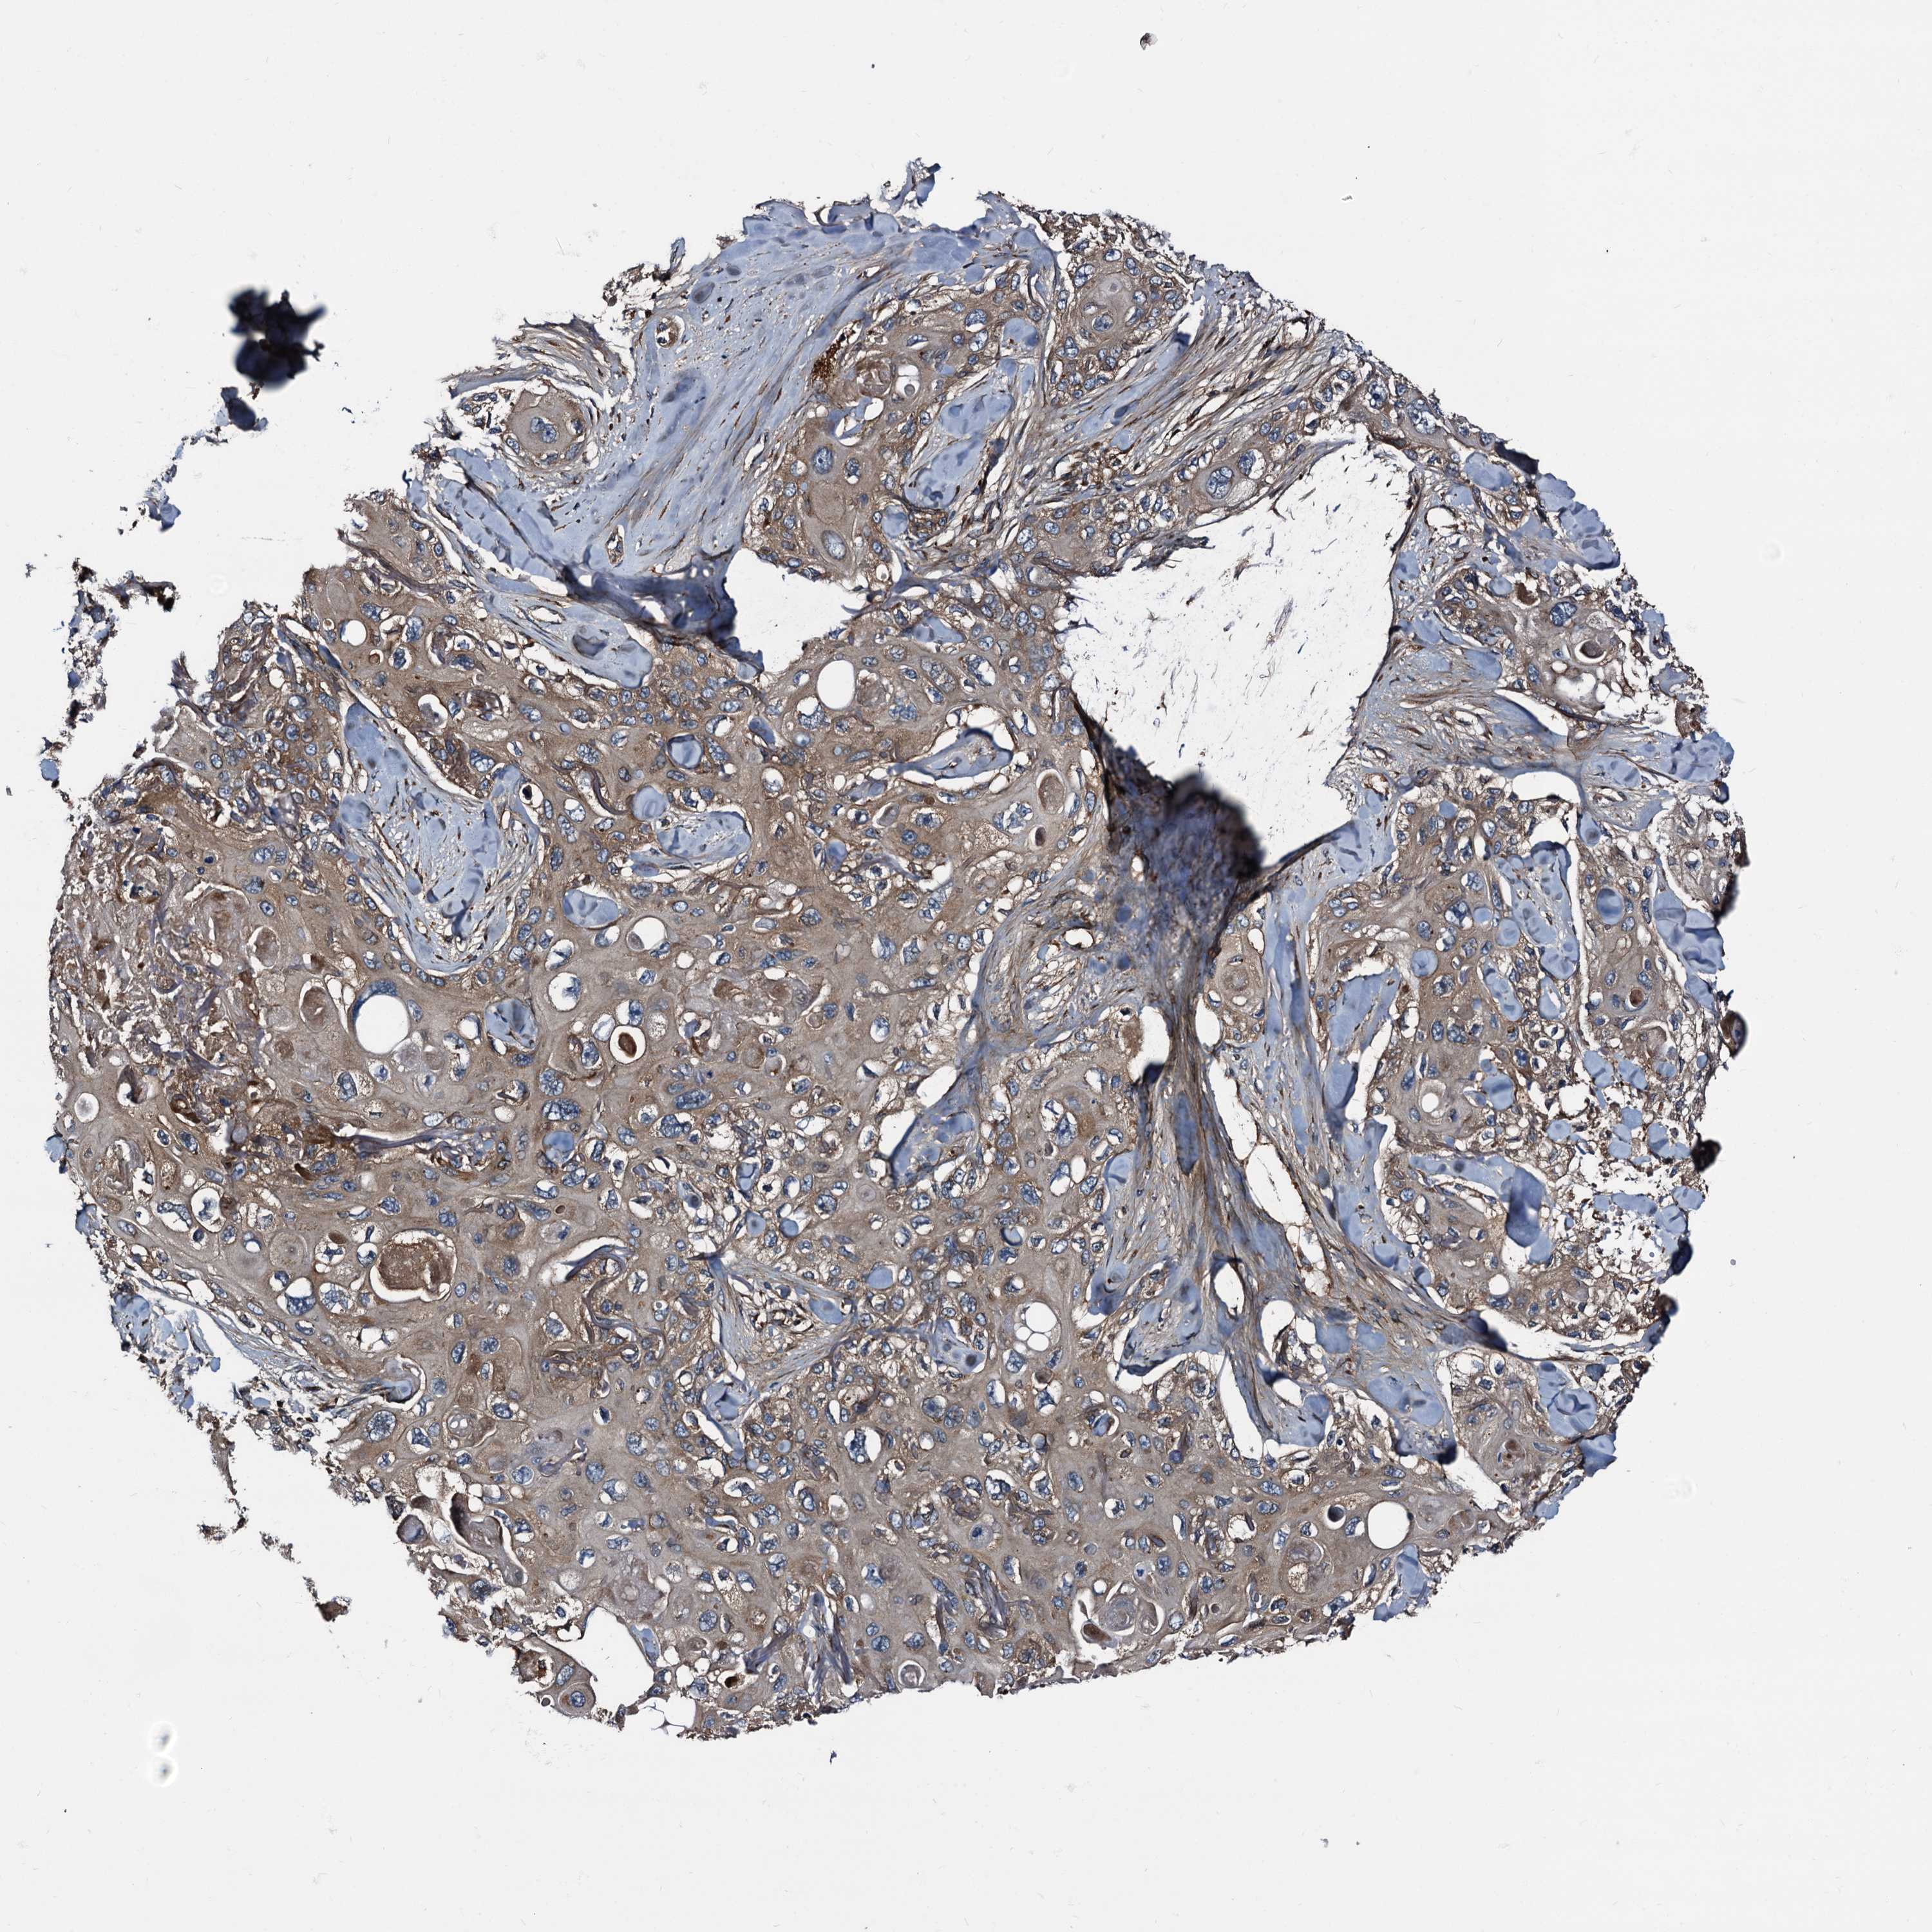

SKIN CANCER - Protein expressioni

A mouse-over function shows sample information and annotation data. Click on an image to view it in a full screen mode. Samples can be filtered based on level of antibody staining by selecting one or several of the following categories: high, medium, low and not detected. The assay and annotation is described here.

Each image is clickable and will lead to virtual microscopy that enables deeper exploration of all samples and also displays staining intensity scores, fraction scores and subcellular localization as well as patient and tissue information for each sample.

Antibody HPA039259

Basal cell carcinoma